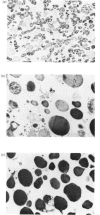

The present study was undertaken to isolate and investigate some physicochemical properties of renin granules from the rat kidney cortex. Two preparations of subcellular organelles were used: a primary-granule fraction, which allowed the properties of lysosomes to be compared simultaneously with those of renin granules, and a semi-purified preparation of the latter. The specific activity of renin in the primary-granule preparations was about 4-fold higher than in the original homogenate; that of the semi-purified renin-granule preparation was about 18-fold higher than in the homogenate, and consisted mainly of electron-dense granules but some mitochondria were also observed. Renin and acid phosphatase release from the primary-granule preparation was increased by lowering osmolality, by a low-molecular-weight solute (glucose) and by Triton X-100 or digitonin. Enzyme release was decreased by lowering the incubation temperature (4 degrees C) or the presence of CaCl2. Renin release from the partially purified granule preparation was not affected by cyclic AMP, cyclic GMP and ATP.

Images in this article